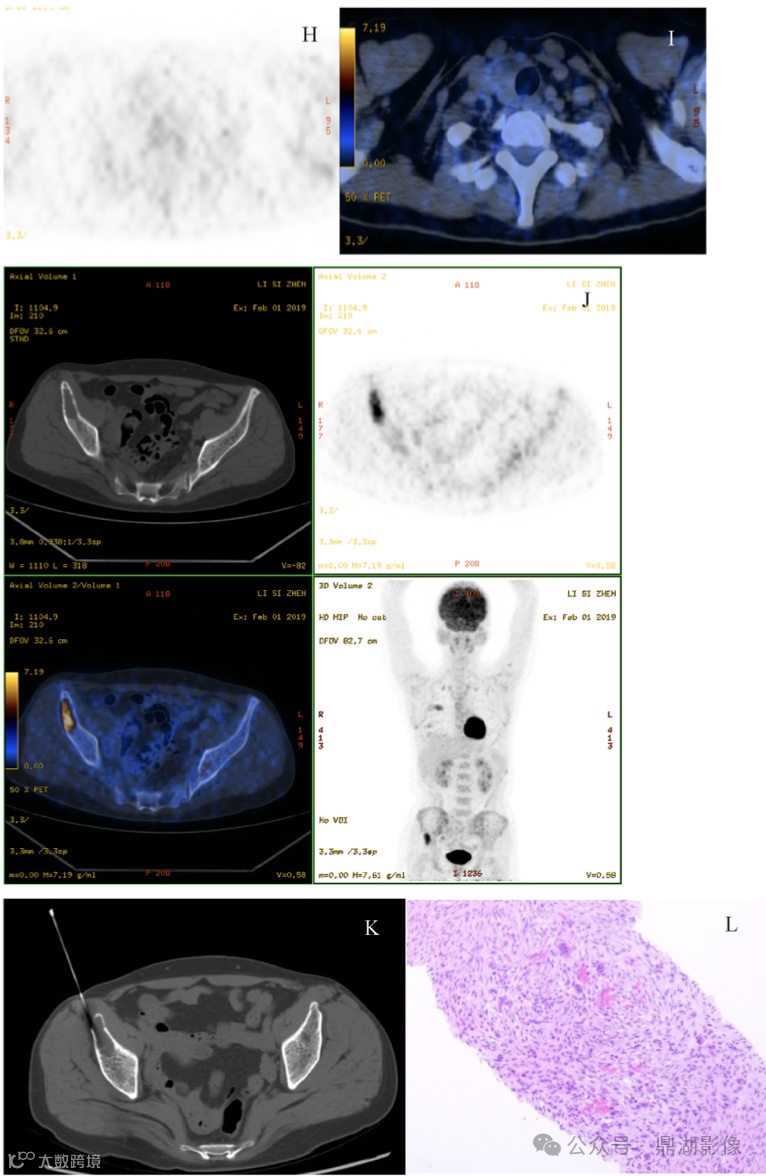

[¹⁸F]FDG PET-CT(图H-J)显示甲状腺右侧叶大小约2.1cm×1.5cm×2.4cm的低密度结节,未见代谢增高,多个肋骨、多个胸腰椎椎体及双侧髂骨见囊性骨质破坏,边缘清楚,未见硬化边,未见钙化及肿块形成,上述骨质破坏区域代谢不均,SUVmax介于1.0-8.0之间,绝大多数病变表现为低密度改变。

基于以上[¹⁸F]FDG PET-CT 表现,患者初步诊断为多发性骨髓瘤,建议针对右侧髂骨病变穿刺活检;患者甲状腺右侧叶未见代谢增高。

J:甲状旁腺肿块内未见代谢增高,多根肋骨、多个胸腰椎及双侧髂骨见囊性骨质破坏区,破坏区内可见不同程度的放射性摄取增高;

K:CT引导下右髂骨骨质破坏区穿刺;

L:肿块镜下形态示梭形细胞伴散在的破骨细胞样巨细胞,伴有反应性类骨质组织及胶原纤维形成(HE,40×)。

碱性磷酸酶932 U/L(参考范围15~121 U/L),甲状旁腺素水平1734 pg/mL(参考范围15-65 pg/mL),血磷0.68 mmol/L(参考范围0.81-1.65 mmol/L),血钙3.21 mmol/L(参考范围1.97-2.85 mmol/L)。

CT引导下行右侧髂骨穿刺活检(图1K),HE染色(图1L,40×)显示梭形细胞及破骨细胞样巨细胞,伴有骨样组织和胶原纤维形成,可见含铁物质沉积。患者行全麻下右侧甲状旁腺切除,术后10分钟血清甲状旁腺素水平下降至223 pg/mL,患者诊断为